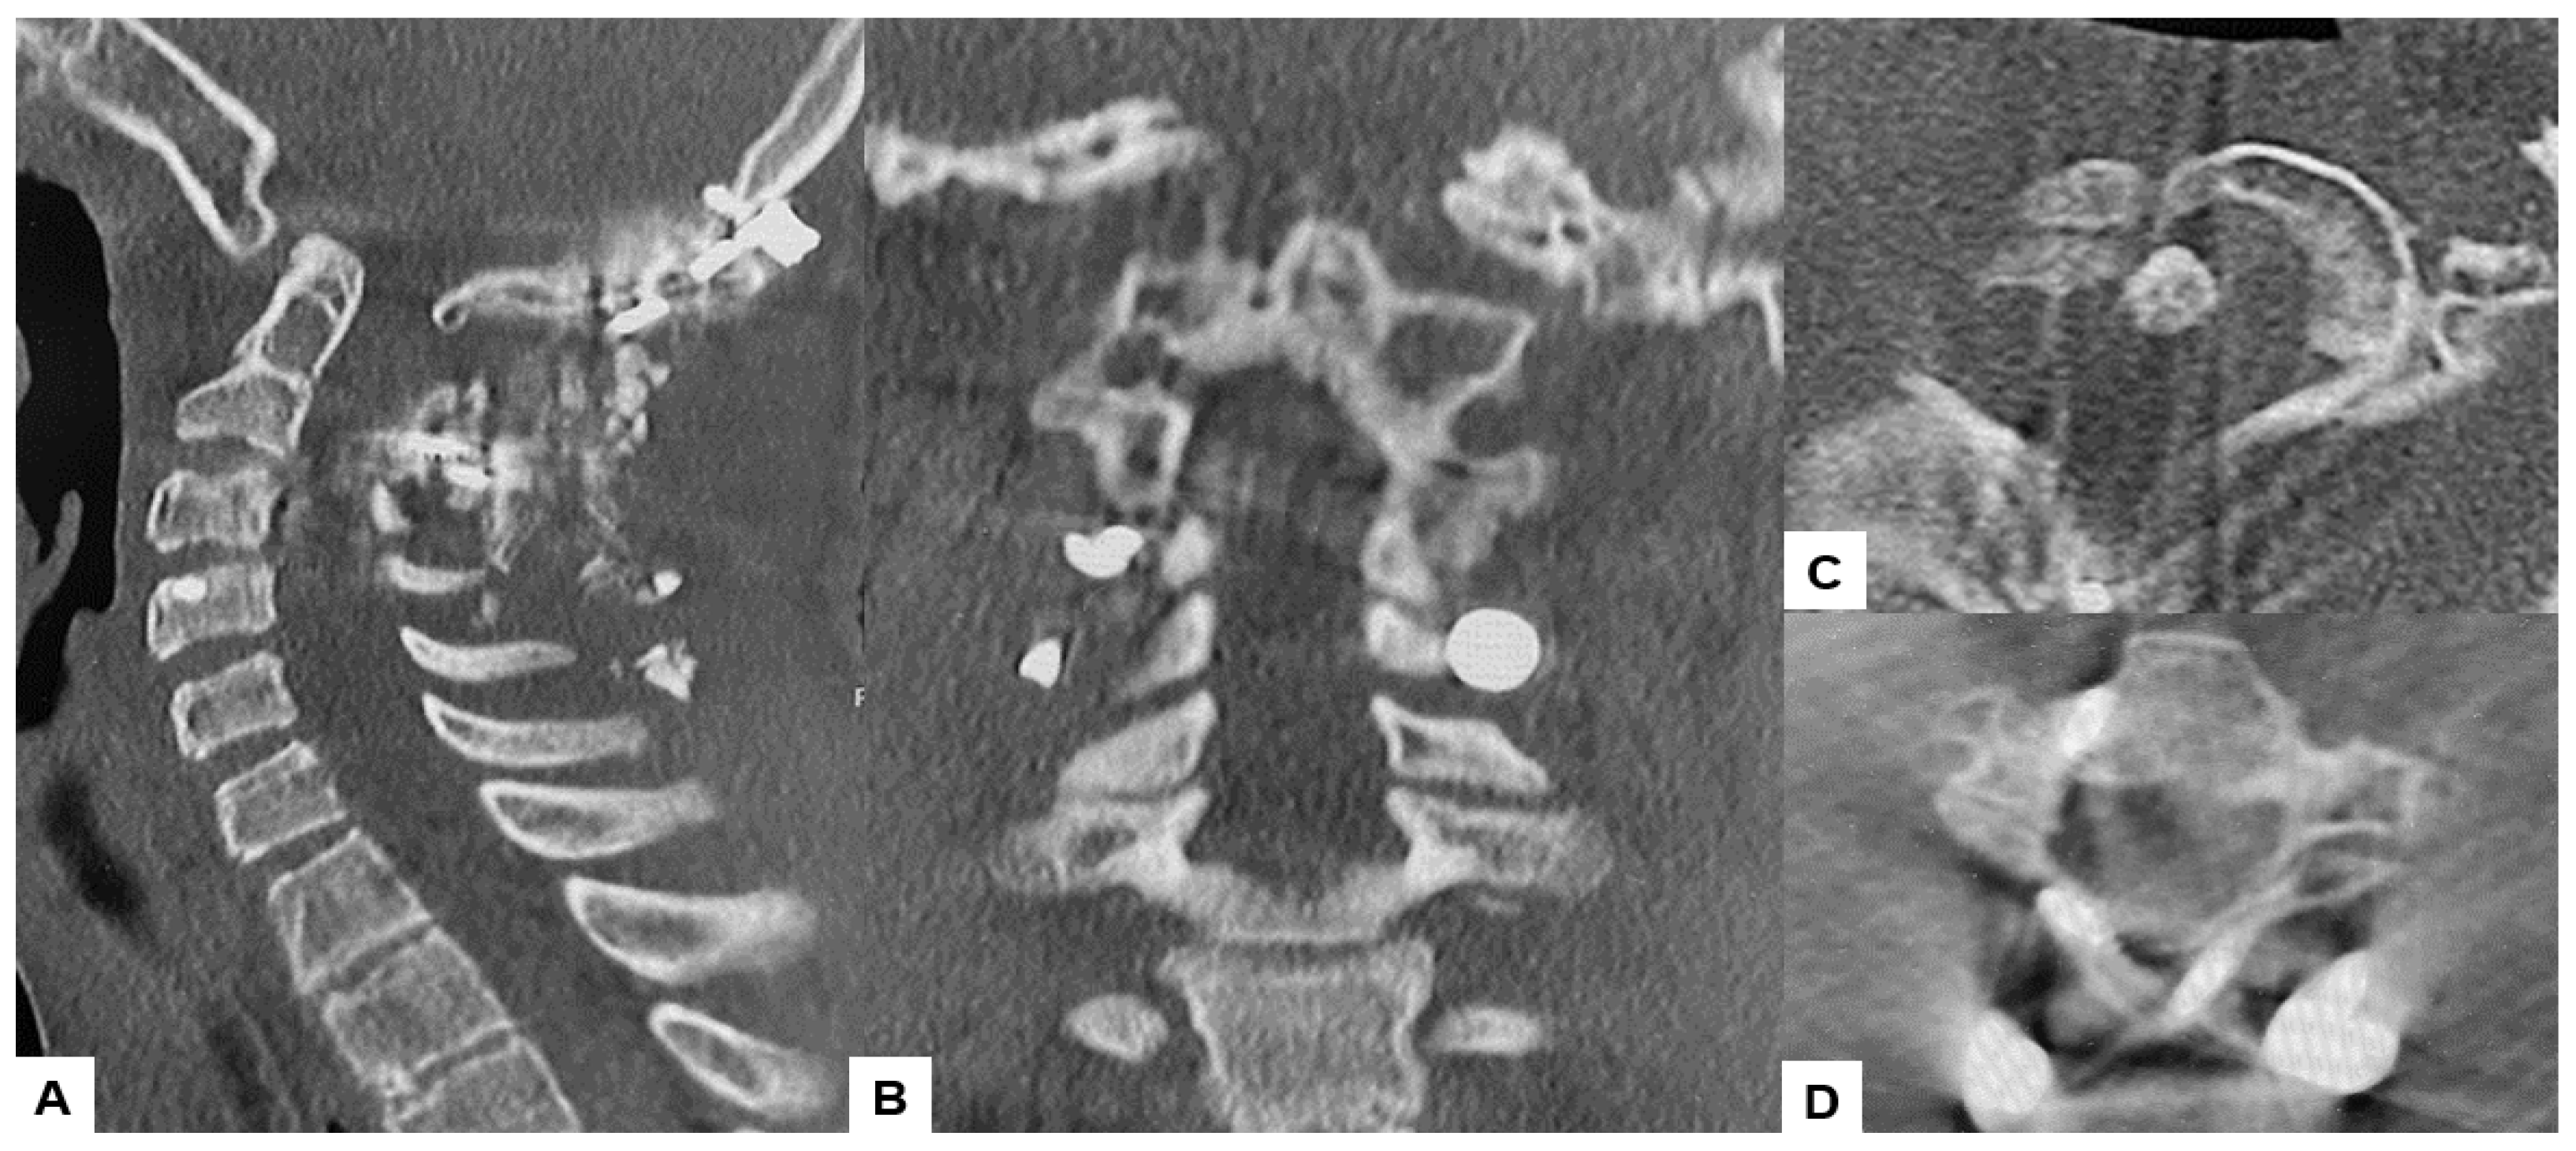

2.5. Postoperative Imaging